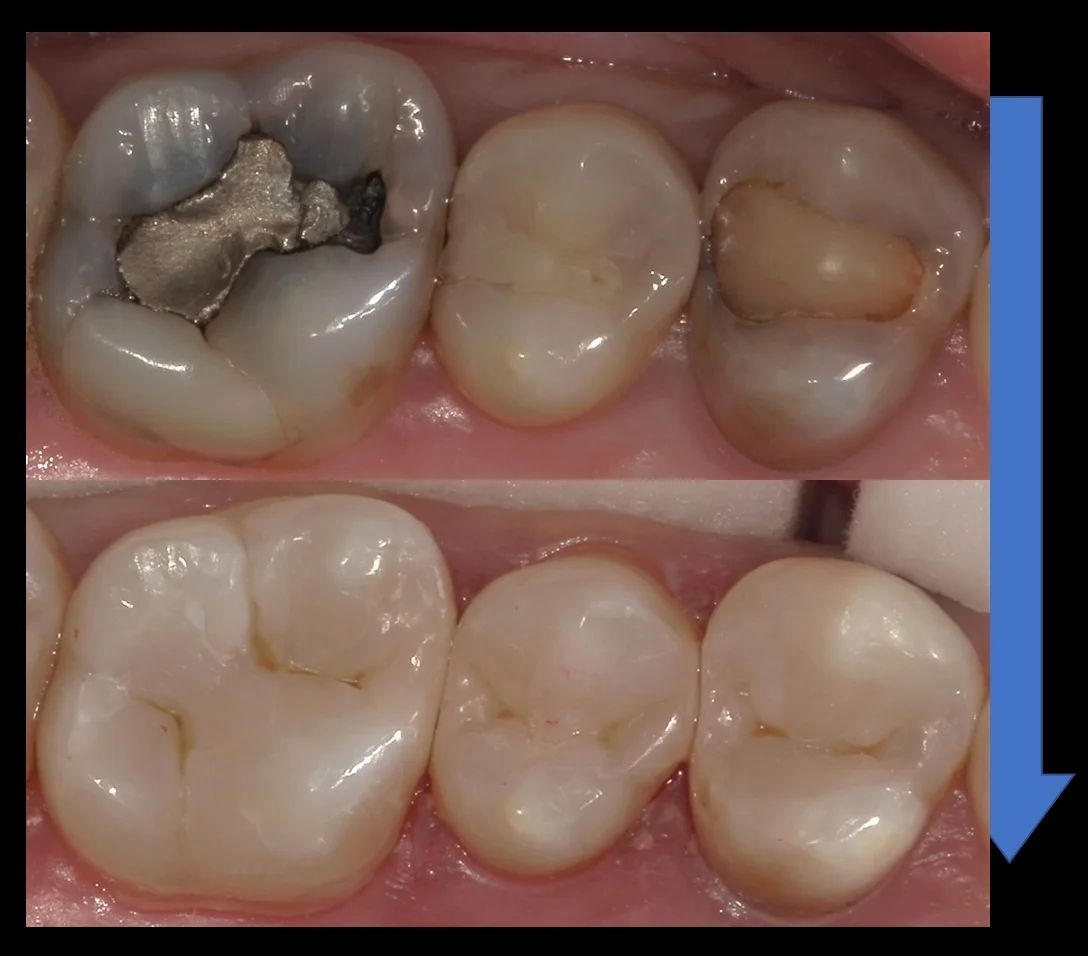

術前術後はこんな感じです。

自然に綺麗に仕上げられたかと思います!

では術前の写真からです。

そして詰め終わったのが、こちらです。

随分と自然な形に仕上げられたかと思います。

そして1カ月後・・・今度はその前後の歯の治療でお越しいただきました。

そして詰め終わったのが、こちらになります。

段差もなく綺麗に詰めることが出来ましたヽ(゚∀゚)ノ パッ☆